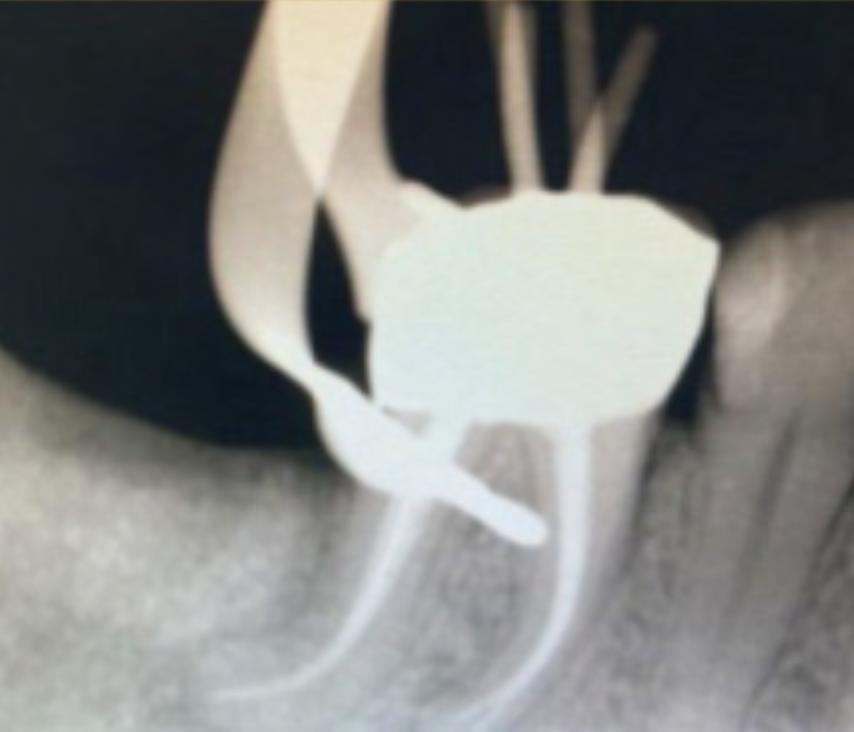

The root canal system was rinsed, dried and then obturated with an hydraulic single cone-technique and bioceramic sealer (BUSA, BC Sealer). Two periapical radiographs with different angulations were taken to verify treatment quality (Fig.3-4).

Clinician’s suspect of unusual anatomy of the distal root anatomy was confirmed by the angulated radiograph that showed an abrupt hidden curvature in the apical third of the canal. Nevertheless the crown-down approach (shaping the coronal and middle part first, thus reducing coronal interferences) and the Fig.3 Fig.4

proper selection of very flexible and resistance instruments, combined with a safer reciprocating clinical motions, allowed to properly negotiate the hidden curvature with no iatrogenic errors . The X7 instruments were chosen because their innovative manufacturing process which provides them with unprecedented flexibility and resistance to cyclic fatigue, allowing practitioners to perform procedures that would be difficult, if not unimaginable, with traditional non-heated files. More precisely, EdgeEndo has focused research and development in the heat-treatment of NiTi files and has developed a proprietary process to produce FireWire™ files that exhibit 2 to 8 times the resistance to cyclic fatigue (and flexibility) than other NiTi files. The benefits of a flexible file seem obvious in complex curvature, but martensitic X7 files also offer another advantage: less “shape memory”. Although shape memory may seem beneficial, it can cause a file to “bounce back” in the tooth, putting lateral pressure on the canal wall, potentially leading to canal transportation or ledging. The present case shows how the excellent clinical performance of X7 files in a very complex anatomy, by avoiding the above mentioned , common iatrogenic errors.